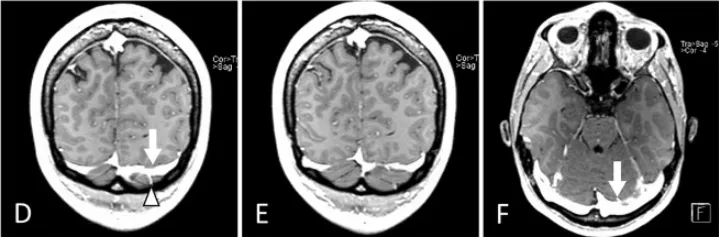

术前(A)及术后(B)正中矢状位MRCISS成像显示:松果体囊肿导致中脑导水管狭窄(箭头标示),但未引发脑积水。术后影像(B)证实囊肿完全切除,中脑导水管恢复通畅。开颅手术范围延伸至横窦区域(箭头标示)。患者临床症状完全消失。手术入路选择基于增强T1加权磁共振成像(冠状位D、E,轴位F)评估:左侧优势静脉窦及桥静脉分布情况,最终选择静脉窦穹隆较高的右侧入路。小脑幕倾斜度分析表明:旁正中入路(G)至松果体区的视角轨迹较中线入路(H)更为平缓。